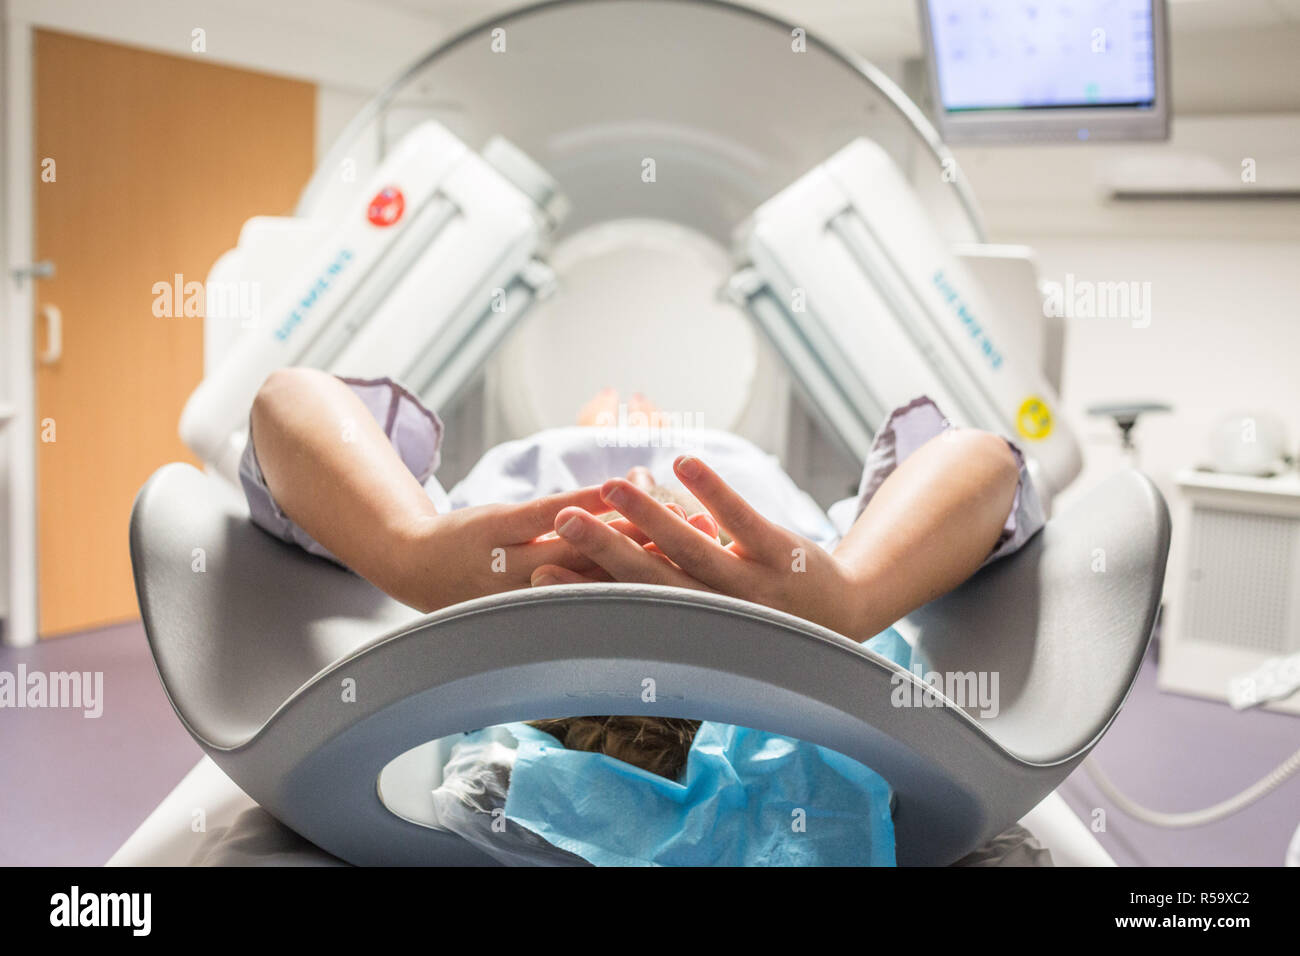

RMKP9GEB–À l'aide d'une scintigraphie couplée à un scanner, l'installation du patient par des techniciens en radiologie, Hôpital d'Angoulême, France.

RMKP9GG2–À l'aide d'une scintigraphie couplée à un scanner, l'installation du patient par des techniciens en radiologie, Hôpital d'Angoulême, France.

RMKP9GE2–À l'aide d'une scintigraphie couplée à un scanner, l'installation du patient par des techniciens en radiologie, Hôpital d'Angoulême, France.

RMKP9GFM–À l'aide d'une scintigraphie couplée à un scanner, l'installation du patient par des techniciens en radiologie, Hôpital d'Angoulême, France.

RMR59XBW–À l'aide d'une scintigraphie couplée à un scanner, l'installation du patient par des techniciens en radiologie, Hôpital d'Angoulême, France.

RMR59XCE–À l'aide d'une scintigraphie couplée à un scanner, l'installation du patient par des techniciens en radiologie, Hôpital d'Angoulême, France.

RMR59XCF–À l'aide d'une scintigraphie couplée à un scanner, l'installation du patient par des techniciens en radiologie, Hôpital d'Angoulême, France.